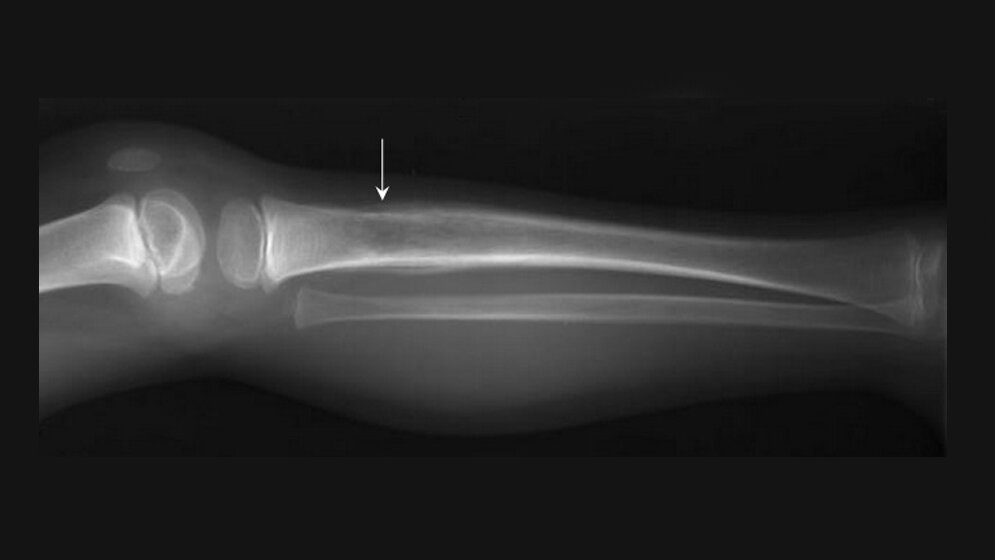

Ewing-Sarkome sind die zweithäufigsten bösartigen Knochentumoren bei Kindern und Jugendlichen. Am Anfang der Erkrankung steht eine einzige spontane Mutation, durch die ein sogenanntes Fusions-Onkogen entsteht. Dieses Fusions-Onkogen aktiviert weitere Gene und setzt einen Prozess in Gang, der den Krebs auslösen kann. In welchem Ausmaß dies geschieht, bestimmen angeborene genetische Variabilitäten der Patienten, sodass es zu unterschiedlich starkem Tumorwachstum kommt. LMU-Wissenschaftler um Thomas Grünewald, Leiter der Max-Eder Nachwuchsgruppe für Pädiatrische Sarkombiologie am Pathologischen Institut der LMU und Abteilungsleiter am Deutschen Krebsforschungszentrum (DKFZ) in Heidelberg, konnten nun zeigen, dass eines der durch das Fusions-Onkogen aktivierten Gene an der Knochenentwicklung beteiligt ist – und dass die Überaktivierung dieses Gens einen vielversprechenden Ansatzpunkt für neue Therapien darstellt. Das Projekt wird von der Deutschen Krebshilfe gefördert.

Derzeitige Therapiestrategien können nicht verhindern, dass es bei etwa einem Drittel der Patienten mit Ewing-Sarkom zu Rückfällen mit oft fatalem Ausgang kommt. Grünewald sucht deshalb nach neuen therapeutischen Optionen. „Das Fusions-Onkogen selbst ist aus verschiedenen Gründen keine geeignete Zielstruktur. Deshalb versuchen wir, sogenannte Surrogat-Targets zu finden. Das sind beispielsweise Gene, die durch das Fusions-Onkogen aktiviert werden“, sagt Grünewald. „Wir haben uns dabei auf Gene fokussiert, die in der natürlichen Knochenentwicklung eine Rolle spielen, und festgestellt, dass das Gen SOX6 im Ewing-Sarkom hochreguliert ist.“ Dieses Gen ist normalerweise nur kurze Zeit während des Knochenwachstums aktiv und bewirkt dann eine massive Zellteilung. „Als wir das Gen in Ewing-Sarkom-Zelllinien ausschalteten, ging das Tumorwachstum in unseren Modellsystemen signifikant zurück. Wir gehen davon aus, dass SOX6 durch das Fusions-Onkogen dauerhaft aktiviert wird, sodass sich die Ewing-Zellen stark vermehren“, sagt Grünewald.